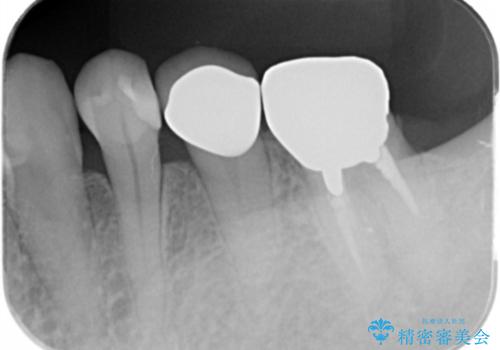

症状もなく、レントゲンでも根尖病巣が見られないため

患者様と話し合った結果、中の土台は外さず、被せ物のみのやりかえとなりました。

レントゲン上で根尖病巣が見られた場合

中の土台を外して根管治療を行わなくてはなりません。

また根尖病巣がなくて土台を変えたい(メタルから白の土台)場合

土台を外すと根管内が細菌感染する恐れがあるために根管治療をやり直す必要があります。